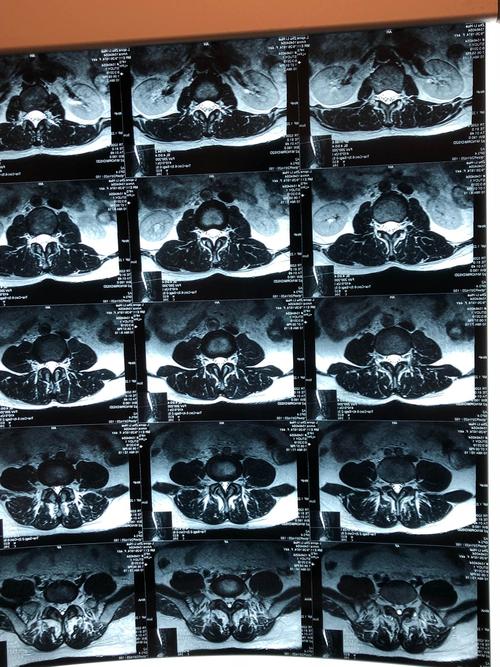

腰椎间盘压迫神经根图,腰1-5神经支配分布图

腰椎mr水平切面,无明显椎间盘压迫神经根情况